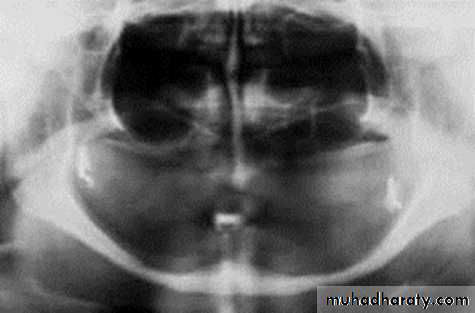

Transosteal / Transosseous Implant

Also called as Staple Bone Implant, Transmandibular ImplantPenetrates both cortical plate and passes through the entire thickness of the alveolar bone

Use restricted to anterior area of mandible

It is not used much any more because they necessitate an extraoral surgical approach.